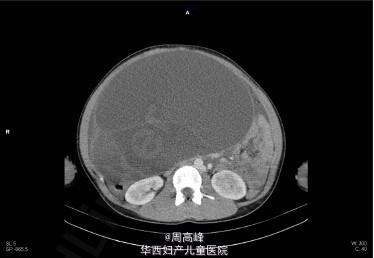

9 公斤卵巢黏液性囊腺瘤一例

近日土耳其 Biçer 医生报道了 1 例罕见病例:14 岁经前期少女,腹内现 9 公斤重的卵巢黏液性囊腺瘤,文章发表在近期的 The American journal of case reports 上。肚子大,不一定是怀孕,怀的还可能是卵巢肿瘤。